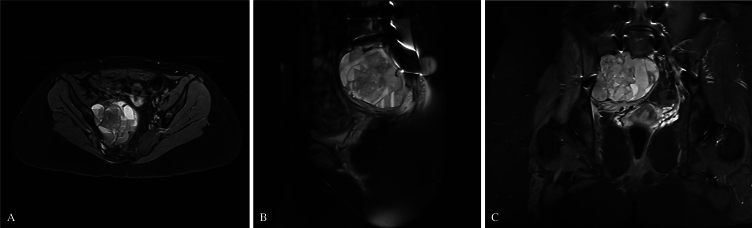

Observations: A 15-year-old girl presented with a 3-month history of right S1-2 radicular pain and right dorsiflexion and plantar flexion weakness. Imaging revealed a right sacral alar aneurysmal bone cyst. The patient underwent right S1-3 hemilaminectomies and partial resection of the S2 and S3 vertebral bodies. Following adequate bony decompression, tumor debulking was performed. Bilateral L4-S1 pedicle screws and left S2AI screws were then placed using neuronavigation guidance. Due to right S1-2 sacral resection, S2AI screw placement was unfeasible. Right-S3 alar-iliac (S3AI) screw placement was performed, and good sacropelvic fixation was demonstrated. Herein, the authors describe the first clinical application of S3AI screw placement in a pediatric patient. After surgery, the patient experienced an improvement in symptoms before later tumor recurrence, which required adjuvant therapy. Long term follow-up revealed solid fusion with stable spinal alignment.

Lessons: In select patients in whom S2AI screw placement is not an option, S3AI screw placement is a feasible, safe, alternative for sacropelvic fixation. https://thejns.org/doi/10.3171/CASE25267.